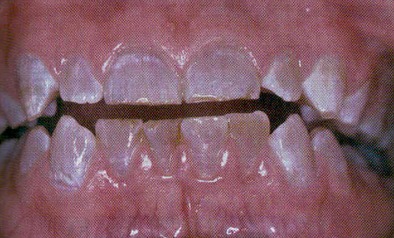

Dental Fluorosis

(The critical period for clinically significant dental fluorosis is during the second and third years of life, when these teeth are developing. Optimum fluoridation of drinking water is around 0.7ppm. Adult toothpaste has 100 parts per million, and fluoride varnish contains several thousand parts per million, but these shouldn’t be ingested, but fluorosis happens during tooth development anyway. Fluorosis is permanent; it is intrinsic staining and doesn’t go away)